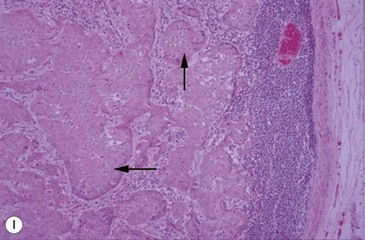

(G) This horse was presented with weight loss and dysphagia. The highly destructive oral and invasive carcinoma was not visible endoscopically from the pharynx and was only seen with difficulty during an oral examination. (H) Photomicrograph of cords of solid squamous cell carcinoma with deep invasion of the tongue. (I) Metastasis of squamous cell carcinoma to regional lymph node showing cords of tumor cells (arrows) beneath cortical lymphoid tissue.

Pathology

Histologically, the tumor has distinctive characteristics with irregular cords of downward-invading neoplastic keratinocytes. (Figs 11.13H,I). A SCC characteristically has large amounts of non-neoplastic fibrous stroma in which inflammatory cells are plentiful. The abundant stroma results in a lesion that is characteristically tough or scirrhous when palpated or excised. The accumulation of variable amounts of keratin produces ‘keratin pearls’ in well differentiated tumors that can be used to define the likely malignancy of the lesion. Poorly differentiated carcinoma shows a more anaplastic cell structure, higher rates of division (high mitotic index), and much less keratin and, therefore, can closely resemble aggressive myxosarcoma. SCC is one of the better defined equine oral neoplasms.